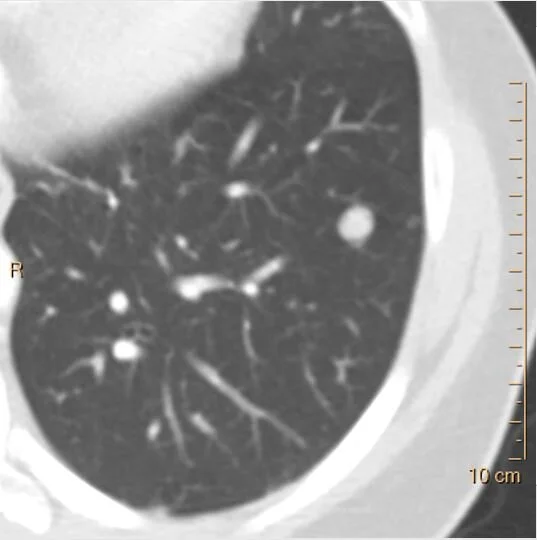

Noncalcified nodule in left lower lobe.